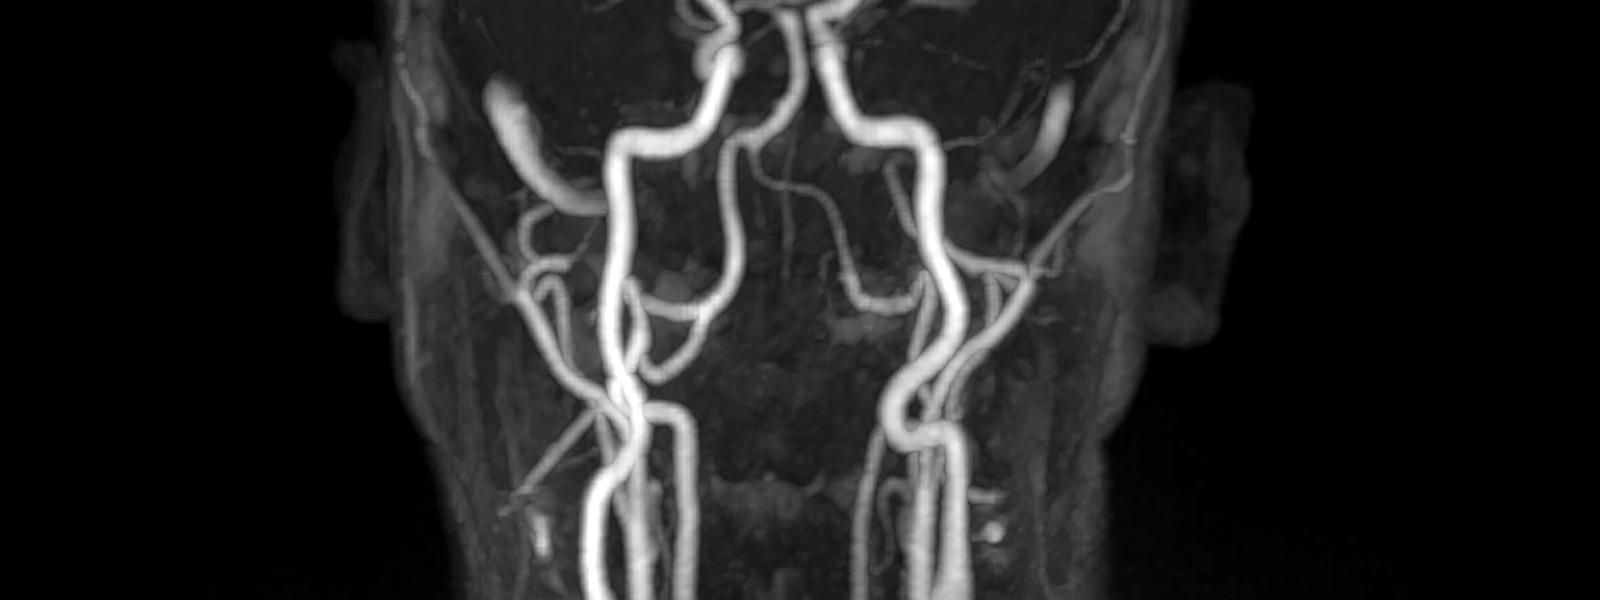

MU Health Care, which performs 700 to 800 neuro interventional procedures each year, began the transition in 2019. The doctors eased into the new technique by using the radial approach only for diagnostic angiograms — a relatively simple procedure that isn't time-sensitive. Unlike the femoral approach, which offers a "straight shot" to the brain, the radial approach requires maneuvering the catheters and wires through a reverse N-shaped path up the arm, down to the aortic arch and up again into the carotid, subclavian or vertebral arteries. They developed a new workflow and found slightly different catheters and wires more suited to the relevant twists and turns.

"Then we started moving into elective treatment of aneurysms, treatment of carotid pathology, vertebral artery stenting, etc., until we moved from A to B," Gomez said. "When you're comfortable with B, you move to C, then to D. At the end of that rainbow was acute stroke intervention. Everything we had learned about the technology and what we could do with the current catheters from the elective interventions, we began to apply to urgent stroke interventions."